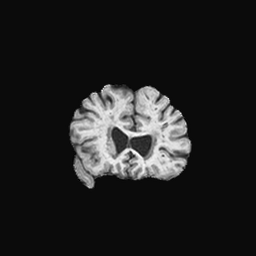

Exp. 1: Segmented adult brain data is used to evaluate our network’s regression performance with known ground truth Tisubscript𝑇𝑖T_{i}. 85 brains from the ADNI data set[1] were randomly selected; 70 brains for ΩtrainsubscriptΩ𝑡𝑟𝑎𝑖𝑛\Omega_{train} and 15 brains for ΩvalidationsubscriptΩ𝑣𝑎𝑙𝑖𝑑𝑎𝑡𝑖𝑜𝑛\Omega_{validation}. Fig. 2 shows an example slice of the ground truth and the reconstructed ΩΩ\Omega.

Figure 2: Example slice from the segmented adult brain MRI data set (a); reconstruction from 300 ωisubscript𝜔𝑖\omega_{i} based on SVRNet regression without SVR (b); SVR initialised with SVRNet predictions after eight iterations of SVR (c). Note that SVRNet (b) predicts individual slice transformations only from image intensities without any initial world co-ordinates of the sampled slice. (d) shows the achieved PSNR in dB when comparing the volumes of (b) and (c) to (a).

Reconstructing from Ti^^subscript𝑇𝑖\hat{T_{i}} initialisation without SVR yields a PSNR of 23.7 ±plus-or-minus\pm 1.09; with subsequent SVR the PSNR increases to 29.5±plus-or-minus\pm2.43 when tested on 15 randomly selected test volumes after four iterations of SVR.